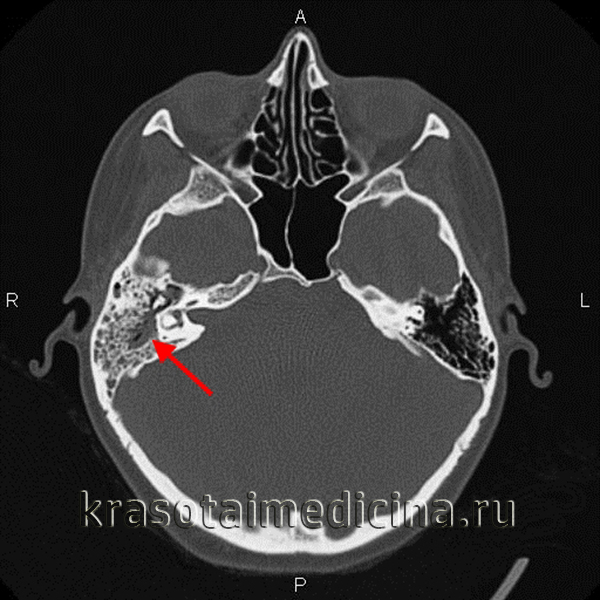

(Справа) При аксиальной КТ височной кости у этот же пациента определяется снижение пневматизации среднего уха и ячеек сосцевидного отростка, наряду с эрозией кортикального слоя сосцевидного отростка (сзади) и слуховых косточек, сопоставимой с отомастоидитом и холестеатомой, что и было подтверждено при операции.

КТ при хроническом отомастоидите с эрозиями слуховых косточек

1. Аббревиатура:

• Хронический отомастоидит (ХОМ)

2. Синонимы:

• Нехолестеатоматозная эрозия слуховых косточек; поствоспалительная эрозия слуховых косточек

3. Определение:

• Эрозия слуховых косточек в отсутствие холестеатомы у пациента с ХОМ

б) Визуализация:

• Костная КТ:

о Необходимо оценить анатомию слуховых косточек:

- Аксиальная КТ/эпитимпанум: «мороженое в рожке» (передняя часть или «мороженое» = головка молоточка; задняя часть или «рожок»=тело наковальни/короткий отросток)

- Аксиальная КТ/мезотимпанум: «две параллельные линии» [передняя линия = сухожилие мышцы, напрягающей барабанную перепонку, идущее к шейке молоточка; задняя линия = лентикулярный отросток наковальни, наковальне-стременной сустав (НСС) и головка стремечка]

- Корональная КТ на уровне длинного отростка наковальни: «прямой угол» (вертикально ориентированный длинный отросток наковальни, горизонтально ориентированный лентикулярный отросток)

о Аксиальная КТ в костном окне:

- Частичное отсутствие одной из «двух параллельных линий» (задней)

о НСС может быть замещен фиброзной тканью:

На аксиальной КТ НСС выглядит расширенным

- Также возникают эрозии «рожка» (тело/короткий отросток наковальни)

о Корональная КТ в костном окне:

- Длинный отросток наковальни чаще всего отсутствует:

Вертикальный сегмент «прямого угла» отсутствует

- Часто обнаруживается втяжение барабанной перепонки

о Типично снижение пневматизации сосцевидного отростка